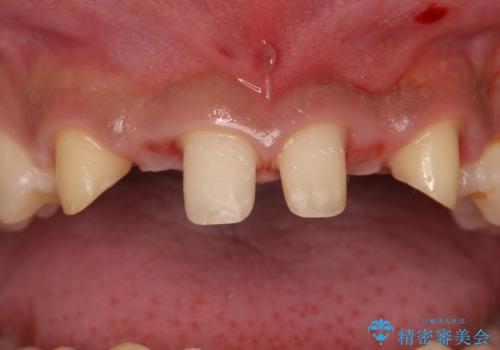

生まれつき上の歯が二本少ない状態でした。

バラバラに位置している前歯の位置を矯正治療で修正してからブリッジを装着しています。

矯正治療によって事前に歯の位置を修正しているため、ダミーの歯の大きさも調整し、自然な仕上がりにしました。また、犬歯のねじれを治してから削っているため、神経をとらずに歯の形を整えることができました。